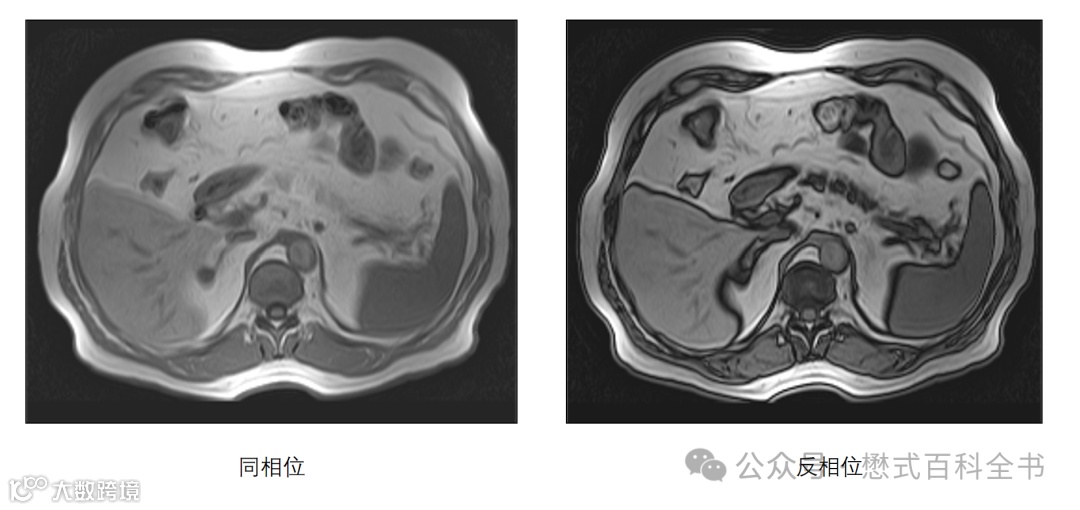

图3:双回波同反相位,反相位产生的勾边伪影

对于双回波同反相位,如果两个回波时间刚好对应水脂的同相位和反相位。

假设一个体素内既含有水,又有脂肪组织。在同相位,产生的MRI信号是水中的氢质子和脂肪组织中氢质子之和。

图4、5:同相位,水脂相位一致,体素内有信号

假设一个体素内既含有水,又有脂肪组织。在反相位,由于水中的氢质子和脂肪组织中氢质子相位相差180°,刚好相反,相位抵消,则累计的MRI信号刚好抵消(即使没有完全抵消,综合的信号也非常小,大大降低)。该体素表现为信号丢失,反应为没MRI信号的黑色(黑带)。

图5、6:反相位,水脂相位抵消,体素内信号下降或者丢失